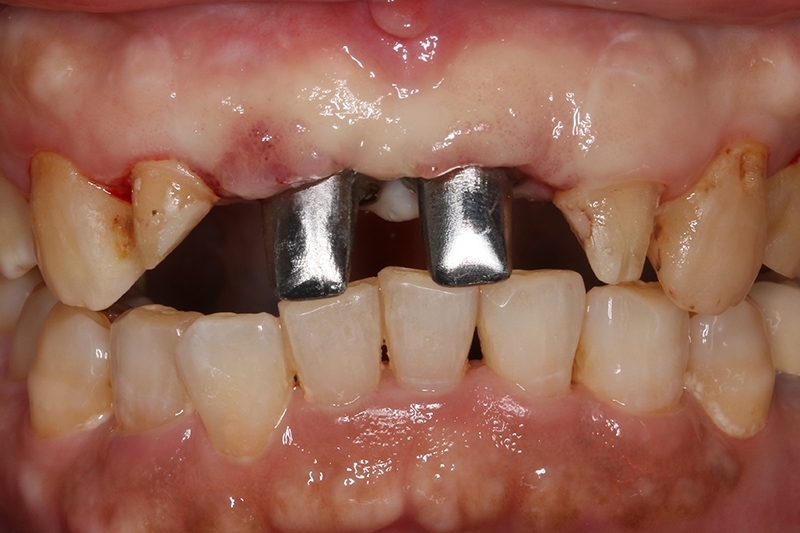

等待2個月進行植牙臨時假牙試戴

客製化金屬支台齒

植牙臨時假牙試戴2週恢復狀況

臨時假牙微笑照